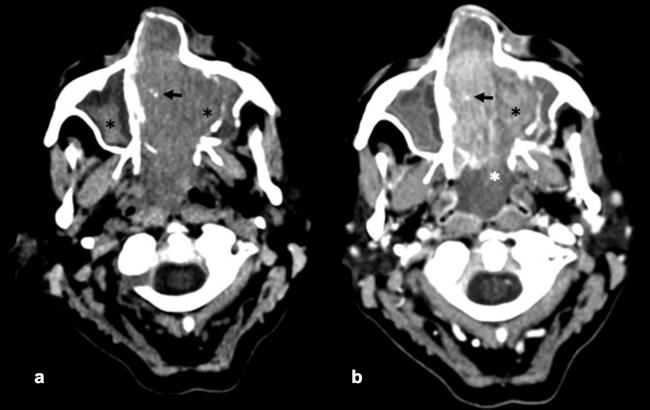

La TC de corte fino (espesor de corte de 1 mm) con reconstrucciones en plano coronal y sagital, es la mejor prueba de imagen inicial para el estudio del NBO. En la TC, aparece como una masa homogénea de tejido blando en la bóveda nasal con realce moderado y uniforme (►Figs.1y2). Se pueden encontrar calcificaciones punteadas dispersas (►Figs.2,3,4,5a,6).50 El valor principal de la TC es una mejor definición de la afectación ósea en comparación con la RM. La TC ayuda a evaluar la erosión ósea de la placa cribiforme, la fóvea etmoidal y la lámina papirácea (►Figs.1,2,3,4,5a,8). Sin embargo, la remodelación ósea sin erosión puede presentarse en algunos casos debido a su patrón de crecimiento indolente.3,35,49 Los estudios de TC generalmente revelan un patrón lítico y muy raramente hiperostosis dominante que simula displasia fibrosa.51 La TC también es útil para evaluar la presencia de metástasis regionales en cuello y a distancia.52,53